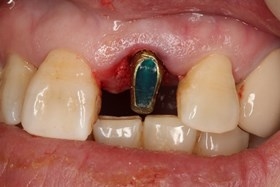

植牙後,立即利用舊牙套轉換成臨時性假牙。

假牙完成後,門牙特寫、切端特寫照,暴牙已不復見